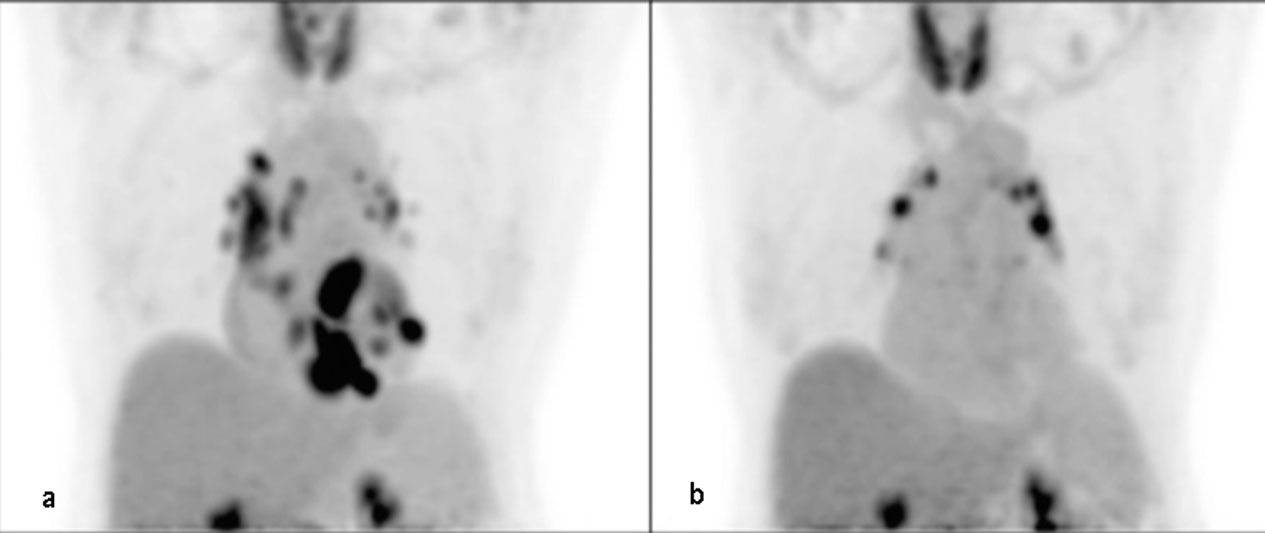

Fig. 3.

Fig. 3.FDG-PET of a 63-year-old female on methotrexate for cardiac sarcoidosis before (a) and during (b) therapy with methotrexate for 2 years, exhibiting a significant decrease in FDG uptake in the heart suggesting adequate response to therapy. The scan continues to show FDG uptake in mediastinal lymph nodes (Bremer et al., 2018)